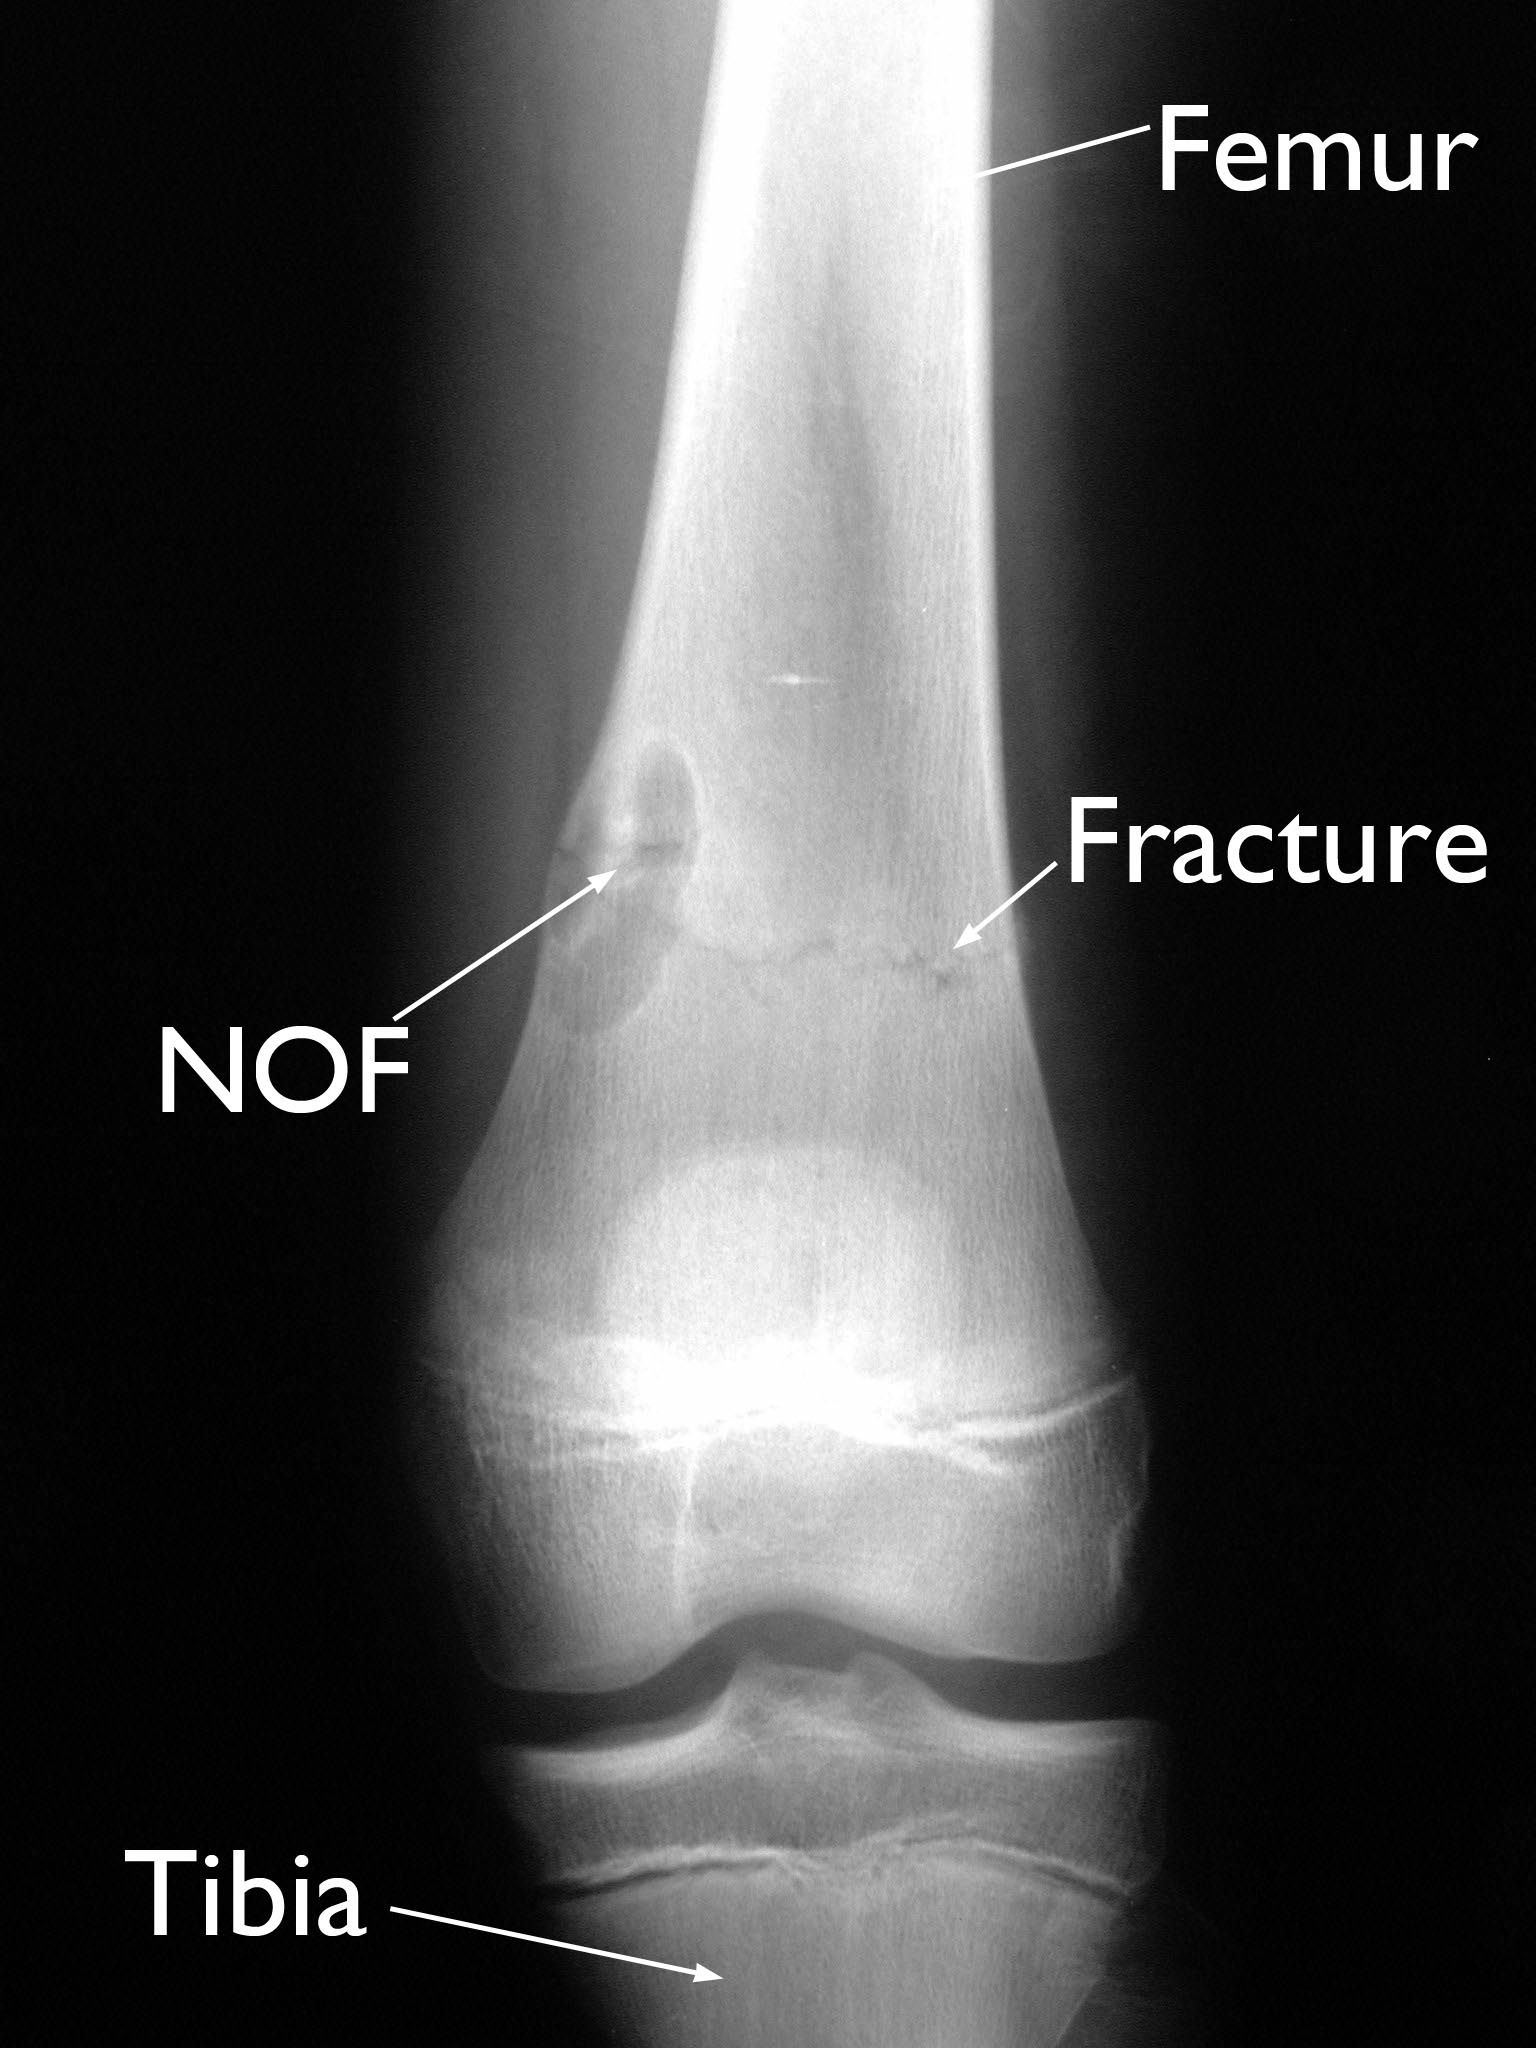

NOF and pathologic fracture in femur

In this X-ray, a pathologic fracture near the patient's knee extends across the lower femur (thighbone) and through an NOF.

• Occasionally, patients will have pain with activity if the NOF is large and has caused the strong outer layer of bone (cortex) to be thinner. Pain may be due to the tumor itself or may be the result of a crack in the bone (pathologic fracture). These minor fractures can occur because an NOF weakens the overall strength of the bone. A fracture is more likely to occur when the NOF is large.